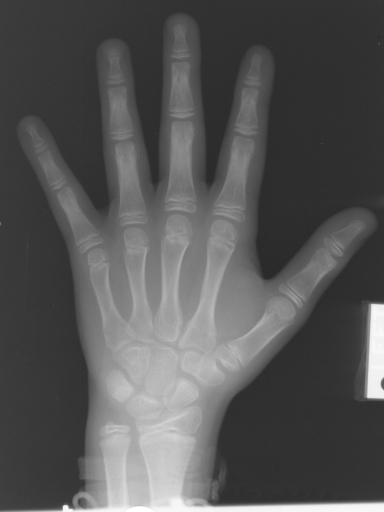

In this section, we report two series of experiments. The first one verifies the correctness or reliability of the micro-DE algorithm to find optimal projections compared to an exhaustive search when we are looking for 4 optimal projection angles out of 16 equidistant angles. In the second experiments, we still provide the results for exhaustive 4/16 selection but examine the evolutionary approach to get 4/180 and 8/180 to investigate the reconstruction accuracy of the micro-DE via correlation of the input image and the reconstructed image using 4/16 (exhaustive), 4/180 (micro-DE) and 8/180 (micro-DE). To conduct the experiments we used 50 images from IRMA dataset [34, 35], a benchmarking collection of 14,400 x-rays images. We selected 10 random classes out of 58 classes, and for each class, we randomly drew 5 images to be used in our experiments. Figure 4 shows the images we have used.

![]() |

[22∘, 68∘, 124∘, 157∘] with |

| [22∘, 68,∘,135,∘, 169∘] with |